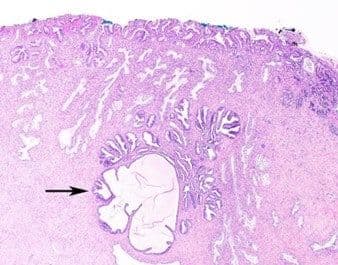

HPV infection may lead to the development of a low-grade (CIN 1) or high-grade squamous intraepithelial lesion (CIN 2 or 3). LSIL development may follow infection by low-risk or high-risk HPV and is thought to depend somewhat on the specific cell population infected (e.g., high-risk HPV infections in the ectocervix, away from the transformation zone, may produce an LSIL-type lesion). LSIL may present colposcopically and microscopically as a flat lesion (Figure 3) or as an exophytic condyloma (Figure 4).

Figure 3

Figure 4

Histologically, the basal layer is somewhat disordered but cytologically bland. There is maturation toward the epithelial surface, where koilocytes may be prominent (Figure 5).

High-risk squamous intraepithelial lesion (HSIL) is associated with infection by high-risk HPV serotypes. HSIL typically presents as a flat lesion (Figure 6), but may also be exophytic, where the colposcopic and microscopic distinction from papillary squamous cell carcinoma (see below) may be challenging.

Figure 6

Histologically, HSIL is characterized by significant architectural disorder, cell crowding, and cytologic atypia in the basal layer. There is generally impaired (CIN 2) or no (CIN 3) maturation toward the epithelial surface, and mitoses are frequently conspicuous in the superficial epithelial layers. Microscopic involvement of endocervical crypts is common (Figure 7) and should be noted in the pathology report.

Figure 7